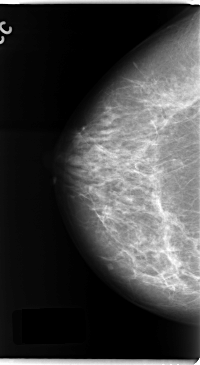

C_0137_1.RIGHT_MLO

RIGHT_CC LINES 4744 PIXELS_PER_LINE 2600 BITS_PER_PIXEL 12 RESOLUTION 50 NON_OVERLAY

RIGHT_MLO LINES 4752 PIXELS_PER_LINE 2624 BITS_PER_PIXEL 12 RESOLUTION 50 NON_OVERLAY